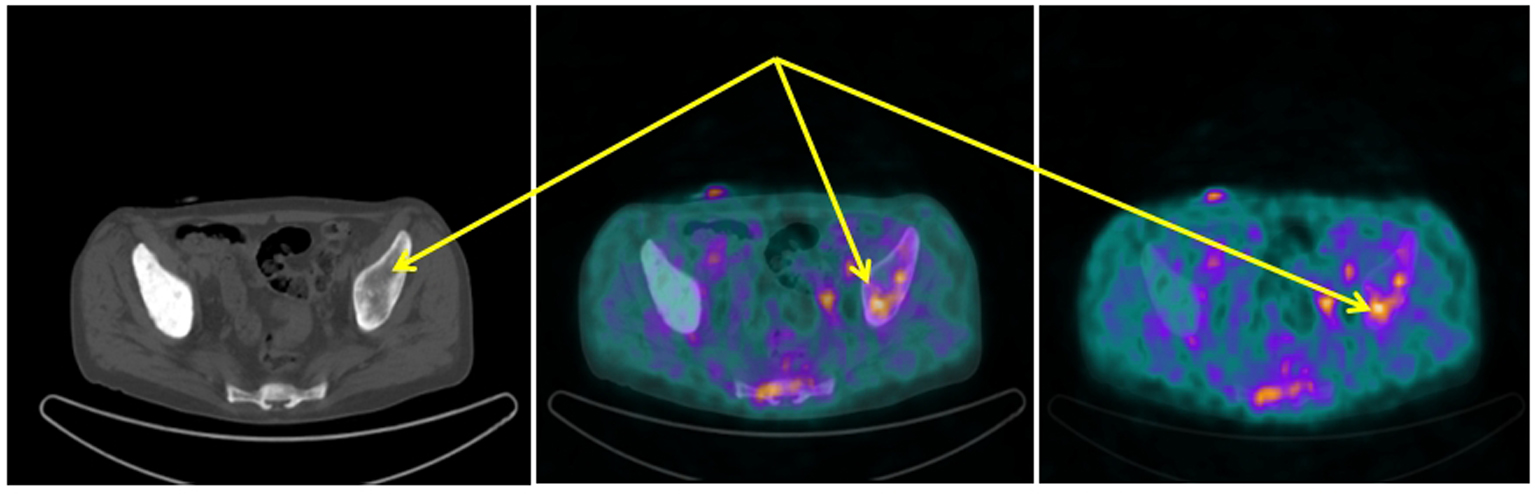

[68Ga-DOTA,1-Nal3]octreotide (68Ga-DOTANOC) PET/CT showed several areas of increased uptake located in bone metastases. The uptake was more significant in metastases with a lytic component on CT (Fig. 1). Moreover, two diffuse areas of increased lung uptake corresponding to lymphangitic neoplastic spreads were noted (Fig. 2). These finding were consistent for an NED of neoplastic cells with overexpression of SSTR2, SSTR3 and SSTR5.

![]() Click for large image | Figure 1. 68Ga-DOTANOC transaxial PET/CT (left CT attenuation correction, middle fused PET/CT, right PET only) showing increased uptake of the radiopharmaceutical in the left sovra-acetabular region corresponding to a mixed (predominantly lytic) skeletal metastasis (arrows). |